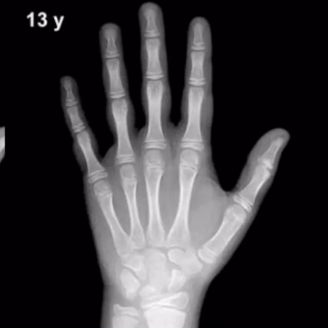

对孩子的手和手腕部X线检查,确定骨龄,判断骨骼是否生长过快。

△ 手和腕部X线检查测骨龄